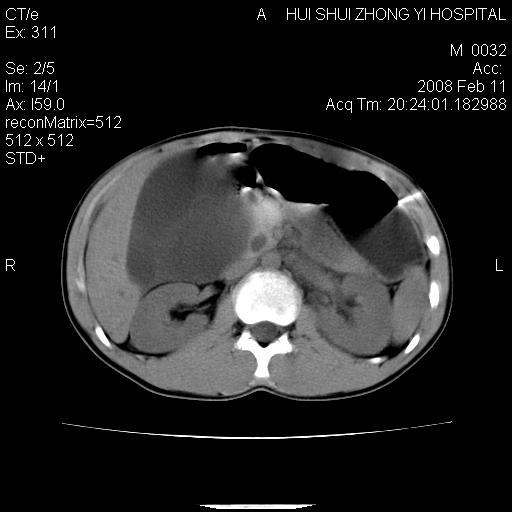

8年前曾在贵洲省人民医院b超诊断为肝内胆管结石。现腹痛剧烈,现发烧、头痛、恶心呕吐县医院b超示胆囊肿大大小159*46mm,囊内见6*5mm强回声光团,胆各总管内径56mm。提示:胆囊结石、急性胆囊炎、胆总管重度扩张。

胆囊结石.急性胆囊炎.重度胆管扩张.右侧胸腔少量积液,建议ct增强

考虑先天性胆管囊肿;胆囊增大并结石。右侧胸腔少量积液,建议ct增强。

caroli囊肿并囊内结石。胆囊增大并胆结石。典型!

先天性胆管囊肿,胆囊结石、胆囊增大,右侧少量胸腔积液。